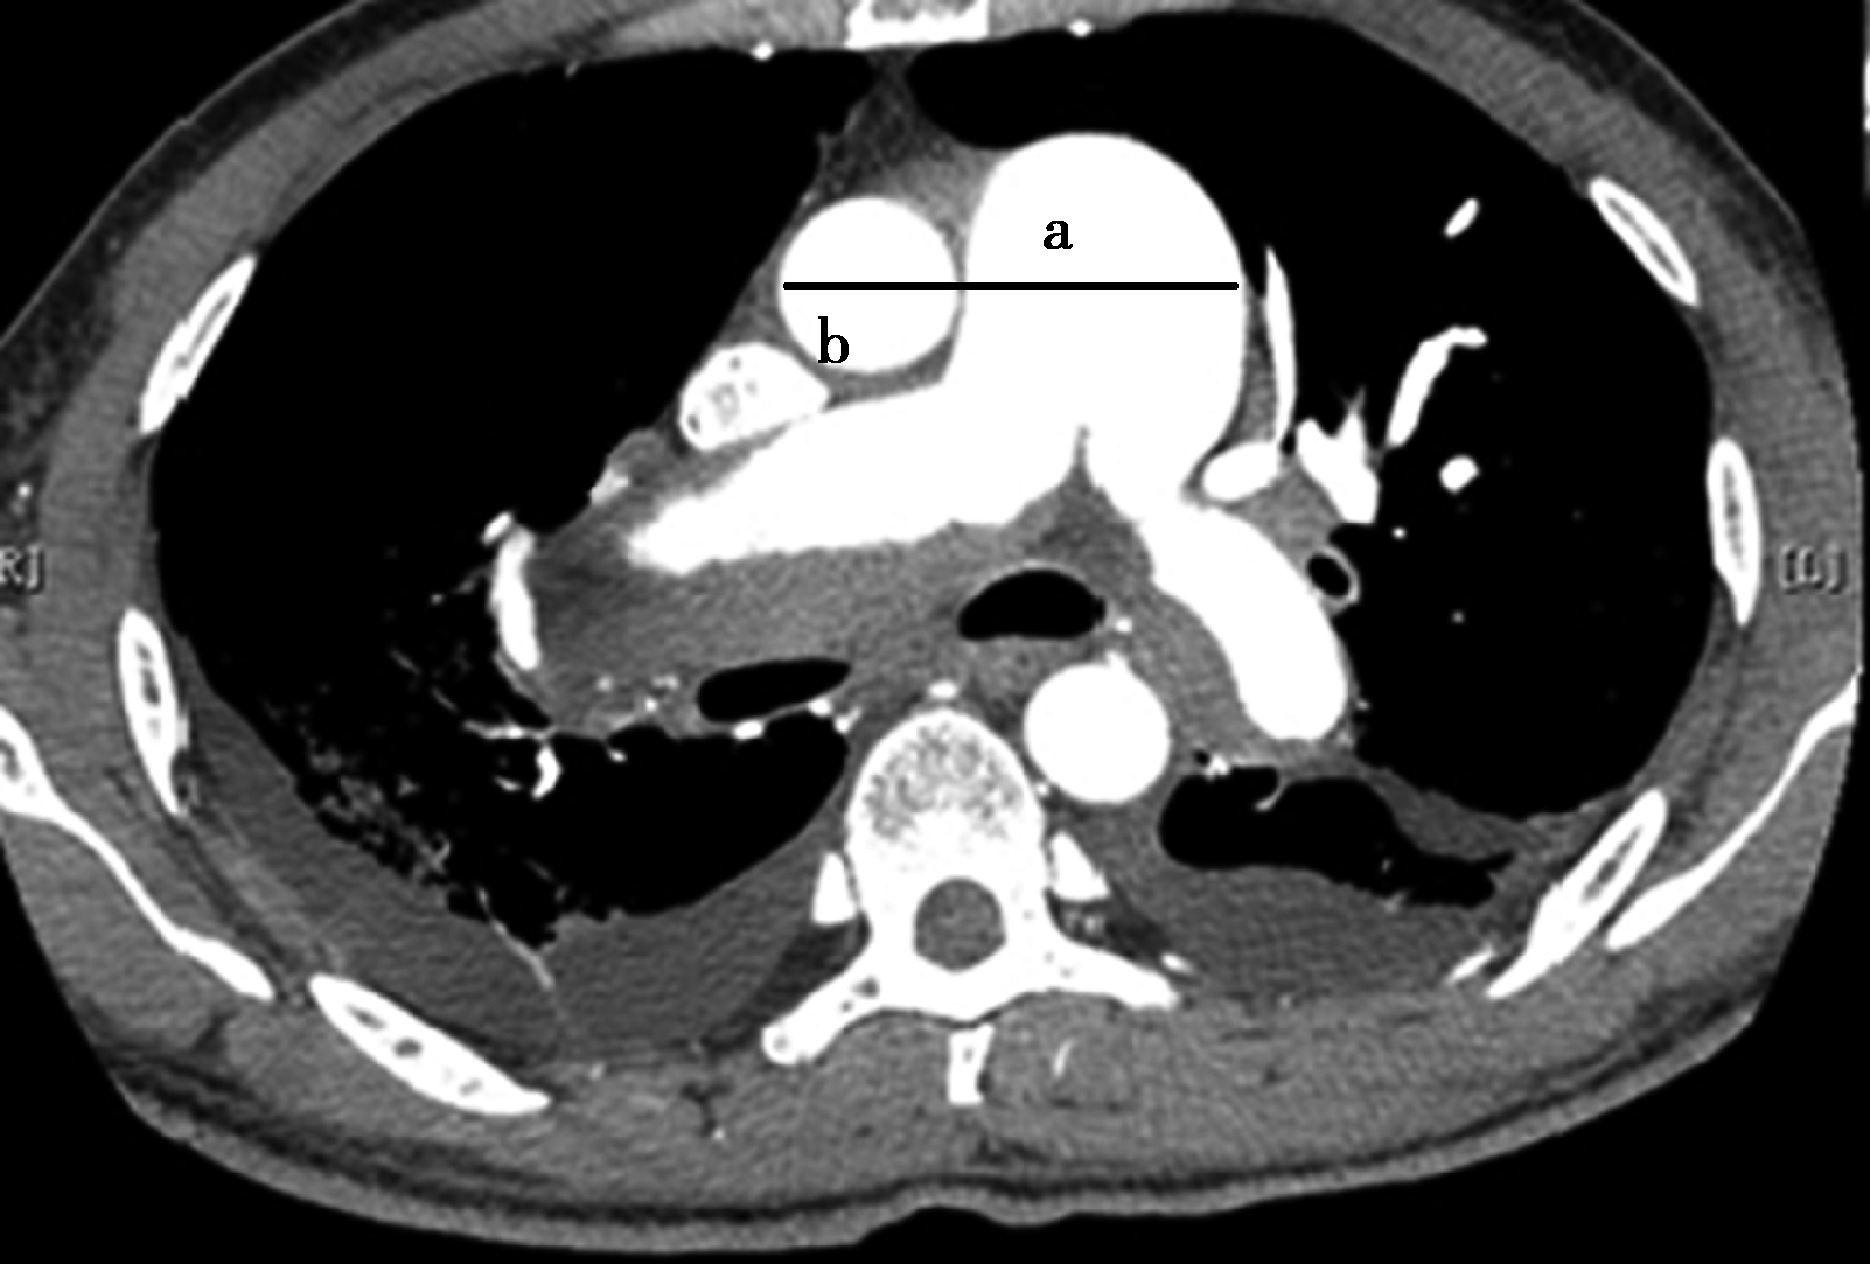

5.主肺动脉增宽

主肺动脉正常较同水平升主动脉直径增粗时或绝对值大于29mm,90%患者为肺动脉增宽,如同时合并右心室扩大,则一般反映为右心负荷增大或肺动脉高压表现(图8-4-8)。

图8-4-8 急性肺栓塞的间接征象

A.轴位CT图像测定主肺动脉直径增宽,大于同水平升主动脉直接(横径a>b);B.右心室增大(横径a>b)